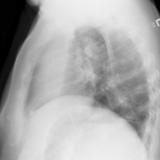

LUL Collapse Case 3 Lateral

Date: 02/19/2004

Views: 3369